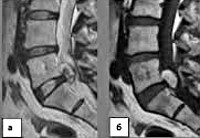

При постановке предварительного диагноза учитывается внезапность возникновения симптомов, их связь в физической активностью, типичная этапность (вначале боль, а затем слабость и онемение конечностей), неврологическая картина. Однако установить диагноз эпидурального кровоизлияния только по клинической картине не представляется возможным. Необходимо проведение МРТ или КТ позвоночника. МРТ позвоночника является более информативным методом, поскольку позволяет визуализировать эпидуральную гематому и дифференцировать ее от других оболочечных кровоизлияний. Кроме того, МРТ позволяет определить степень сдавления спинного мозга и выявить признаки компрессионной миелопатии. Дополнительно может быть проведена КТ сосудов или магнитно-резонансная ангиография.